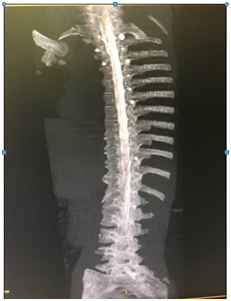

She had MRI brain and C spine with contrast, (Figure 1) a lumbar puncture after imaging, intravenous pain medication, dexamethasone per os, and was positioned supinely. Her brain MRI and C spine showed signs of low intracranial pressure with DME; see in Figure 2. She initially had a traumatic and dry LP with Glucose 5.68, raised protein of 3672 mg, 54000 red cells, 43 white cells and xanthochromia was positive.

Figure 1 white arrow pointing to contrast enhancement.